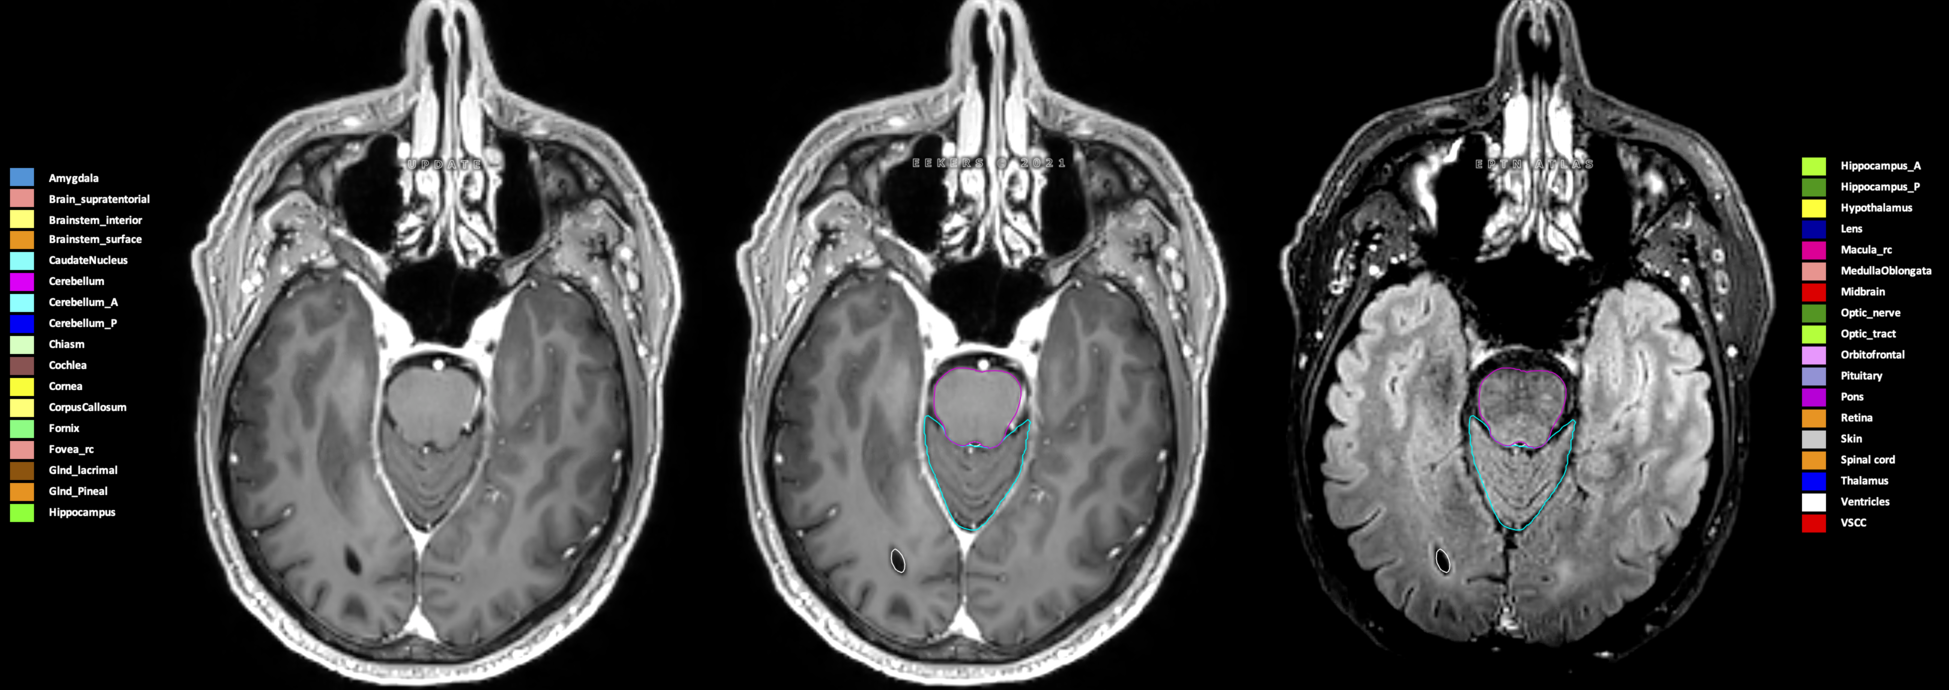

Eekers et al. have published an international neurological atlas for contouring of organs at risk in consensus with the European Particle Therapy Network (EPTN) in 2018 and an update in 2021. The purpose of this consensus atlas is to decrease inter- and intra-observer variability in delineating OARs relevant for neuro-oncology.

Included are all OARs known to be relevant for radiation-induced toxicity in neuro-oncology: brain, brainstem (midbrain, pons, medulla oblongata), chiasm, cerebellum (anterior & posterior), cochlea, cornea, hippocampus (anterior & posterior), hypothalamus, lens, lacrimal gland, optic nerve, pituitary, skin, and vestibular & semicircular canals. To further facilitate research on cognition, vision and radiological changes after irradiation of the brain, potential clinically-relevant OARs are included: amygdala, caudate nucleus, cerebellum (anterior & posterior), corpus callosum, fornix, macula, optic tract, orbitofrontal cortex, periventricular space (PVS), pineal gland, and thalamus.

Three-dimensional delineation of the 25 consensus OARs for neuro-oncology are shown on CT (WW/WL 120/40, 3000/600), 3T MR images, (T1Gd, T2FLAIR 1mm) and 7T MR (MP2RAGE 0.7 mm). All are presented in transversal, sagittal and coronal view.